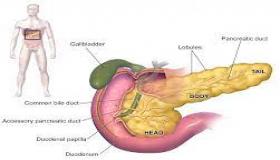

هضم الطعام

ما هو مرض حمض الجزر؟

البنكرياس.